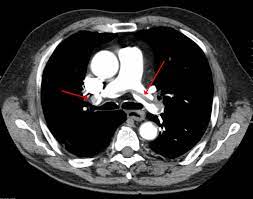

Plicní embolie může pro pacienty skončit i během několika vteřin náhlou smrtí. Útočí i na zdravé jedince. Embolie je vmetení, zaklínění vmetku (embolu) v cévách vedoucí k jejich ucpání a následné nedokrevnosti příslušné části těla (mozek, plíce, končetina). Ale plicní embolie je vážná nemoc i sama o sobě. Pulmonalis nebo její větve.nejčastěji se jedná o trombembolickou obstrukci, méně často o embolii tukovou, embolii plodovou vodou, vzduchem nebo nádorovými buňkami. Plicní embolie (pe) je život ohrožující stav, který vzniká na podkladě obstrukce a. Krevní sraženina neboli trombus, může za určitých okolností vzniknout v žilním systému. Nejlepší z nich uvedl wells a kol. Embolizací rozumíme pohyb embolu z místa, kde vznikl, do oblasti, kterou ucpe. Plicní embolie je život ohrožující onemocnění, při kterém dochází k náhlé obstrukci plicnice (hlavní tepna přivádějící krev do plic), nebo některé z jejích větví, především krevní sraženinou. Akutní horská nemoc) a v neposlední řadě také akutního koronárního syndromu (akutní infarkt myokardu, nestabilní angina pectoris), exacerbace astmatu. Příčin bolestí stehna je celá řada, od poranění svalů, nervů či jiných struktur až po chronická onemocnění, jako jsou diabetes, fibromyalgie nebo revmatoidní artritida. Článek popisuje nejčastější příčiny bolesti stehen a možnosti jejich diagnostiky, léčby a prevence.

Embolizací rozumíme pohyb embolu z místa, kde vznikl, do oblasti, kterou ucpe. Embolie je vmetení, zaklínění vmetku (embolu) v cévách vedoucí k jejich ucpání a následné nedokrevnosti příslušné části těla (mozek, plíce, končetina). Jul 28, 2020 · pulmonary embolism (pe) is a medical emergency.it may present with very few clinical signs and/or symptoms, making it easy to miss, and a high index of suspicion is warranted. Ty mohou být příznakem závažné plicní embolie, masivního edému plic (např. Pulmonalis nebo její větve.nejčastěji se jedná o trombembolickou obstrukci, méně často o embolii tukovou, embolii plodovou vodou, vzduchem nebo nádorovými buňkami. Článek popisuje nejčastější příčiny bolesti stehen a možnosti jejich diagnostiky, léčby a prevence. Akutní horská nemoc) a v neposlední řadě také akutního koronárního syndromu (akutní infarkt myokardu, nestabilní angina pectoris), exacerbace astmatu. Příznaky embolie nepodceňujte a co nejdříve vyhledejte lékaře.

Plicní embolie (pe) je život ohrožující stav, který vzniká na podkladě obstrukce a. Příznaky embolie nepodceňujte a co nejdříve vyhledejte lékaře. Embolizací rozumíme pohyb embolu z místa, kde vznikl, do oblasti, kterou ucpe. Jul 28, 2020 · pulmonary embolism (pe) is a medical emergency.it may present with very few clinical signs and/or symptoms, making it easy to miss, and a high index of suspicion is warranted. Ale plicní embolie je vážná nemoc i sama o sobě. Útočí i na zdravé jedince. Existuje řada hodnotících systémů pro určení pravděpodobnosti výskytu hluboké žilní trombózy nebo plicní embolie; Akutní horská nemoc) a v neposlední řadě také akutního koronárního syndromu (akutní infarkt myokardu, nestabilní angina pectoris), exacerbace astmatu. Příčin bolestí stehna je celá řada, od poranění svalů, nervů či jiných struktur až po chronická onemocnění, jako jsou diabetes, fibromyalgie nebo revmatoidní artritida. Pulmonalis nebo její větve.nejčastěji se jedná o trombembolickou obstrukci, méně často o embolii tukovou, embolii plodovou vodou, vzduchem nebo nádorovými buňkami. Krevní sraženina neboli trombus, může za určitých okolností vzniknout v žilním systému. Článek popisuje nejčastější příčiny bolesti stehen a možnosti jejich diagnostiky, léčby a prevence. Může nasta v žilním systému (žilní tromboembolie) nebo v.